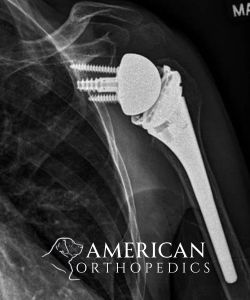

Total Shoulder Replacement

Patient of Dr. Ratner.

After